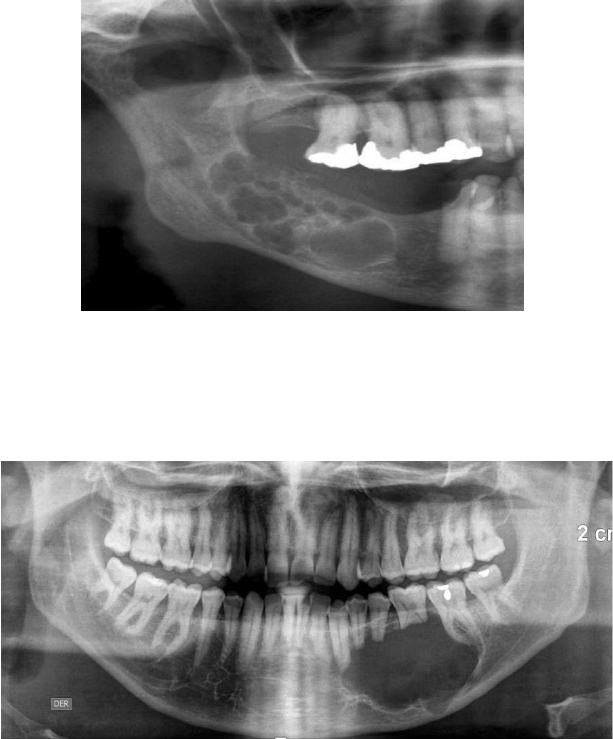

TUMORES ODONTOGÊNICOS EPITELIAIS BENIGNOS Ameloblastoma É de crescimento lento; Assintomático; Acomete mais a mandíbula (ramo da mandíbula e MI) do que a maxila; Expande corticais, tem alta taxa de recidiva; Ocorre em três diferentes situações: Ameloblastoma Multicístico ou sólido: lesões localizadas na mandíbula. Imagem radiolúcida e multilocular, descrita como “favo de mel” ou “bolhas de sabão”. Tem reabsorção óssea, deslocamento dentário e rompimento de corticais ósseas. Ameloblastoma Unicístico: caracteriza-se por estar dentro de um cisto. Tem imagem radiolúcida, circunscrita e bem demarcada. Acomete mais pacientes jovens e o 3° molar. Está associado a dente incluso. Ameloblastoma periférico ou extraósseo: mais incomum. Restos da lâmina dentária, lesão séssil (base alargada) ou pedenculada, mucosa alveolar ou gengiva. Acomete as idades entre 50-60 anos. Tumor Odontogênico Escamoso Pode se confundir com o ameloblastoma; Acomete mais homens, com idade de +/- 39 anos; Assintomático, perda óssea severa; Associado a mobilidade dentária, causa inchaço na região, reabsorção de raízes; Imagem radiolúcida, em forma de triângulo ou semicircular Tumor Odontogênico Epitelial Calcificante Tumor de Pindborg; Acomete mais homens, entre 30-50 anos; Assintomático, de crescimento lento, maior recidiva; Imagem radiolúcida multilocular ou unilocular (menos frequente), margens festonadas; Afeta a região dos M e ramo de mandíbula; Tumor Odontogênico Adenomatoide Acomete mais pacientes jovens, entre 10-19 anos; Mais comum em mulheres; Imagem radiolúcida, unilocular circunscrita, envolve a coroa do dente incluso; Acomete mais caninos; Aspecto de “flocos de neve”; Assintomático, de crescimento lento, não invasivo; Pode ser intra ou extra ósseo; Estende apicalmente ao longo da raiz. TUMORES ODONTOGÊNICOS MESENQUIMAIS Fibroma Odontogênico Causado por uma proliferação ectomesenquimal; Também conhecido como: Fibroma Cemento-Ossificante; Dividido em: fibroma Odontogênico central e fibroma Odontogênico periférico. Fibroma Odontogênico Central: mais raro, assintomático, maior ocorrência em mulheres entre 30-40 anos, raça branca, mandíbula (PM e M). Possui imagem radiolúcida (ou mista), unilocular de bordas bem finidas, expande corticais, de crescimento lento, reabsorve raízes e expansão da tábua óssea vestibular. Fibroma Odontogênico Periférico: crescimento focal, benigno e raro. Ocorre na gengiva, às vezes sem alteração radiográfica. Imagem radiolúcida, sem envolvimento ósseo, deslocamento de raízes e de dentes próximos. Aspecto nodular, séssil, aderida à gengiva, coloração semelhante ao tecido. Mixoma Odontogênico ou Mixofibroma Cementoblastoma Acomete mais a região posterior da mandíbula; Lesão intraóssea expansiva, de crescimento lento; Acomete mais jovens, em torno de 20-30 anos; Assintomática; Imagem radiolúcida, com aspecto “raquete de tênis”; Associada a dentes inclusos; Move dentes adjacentes, expande corticais; Acomete mais pacientes jovens, homens (; Ocorre mais na mandíbula, região de PM e M; Crescimento lento e contínuo, expansão óssea das corticais; Imagem radiopaca, bem definida, circundada por uma zona radiolúcida; Halo radiolúcido, fundida à raiz do dente, de forma circular, bem delimitada. TUMORES ODONTOGÊNICOS MISTOS Fibroma Ameloblástico Odontoma Composto + gressivo; Acomete jovens, homens, em torno de 14-20 anos; Imagem radiolúcida, unilocular ou multilocular, margens bem definidas e bem delimitadas; Associada à dentes inclusos; Expande corticais ósseas, pode deslocar dentes vizinhos; Acomete mais a região posterior da mandíbula (PM e M). Acomete mais entre 20-30 anos; Acomete a parte anterior da maxila, não expande corticais; Imagem patognomônica; Assintomática; Imagem radiopaca e radiolúcida (mista), auto limitante; Odontoma Complexo Idade entre 20-30 anos; Acomete a mandíbula, região do 2º e 3º M; Acomete mais mulheres; Imagem radiopaca, irregular; Não causa expansão óssea.